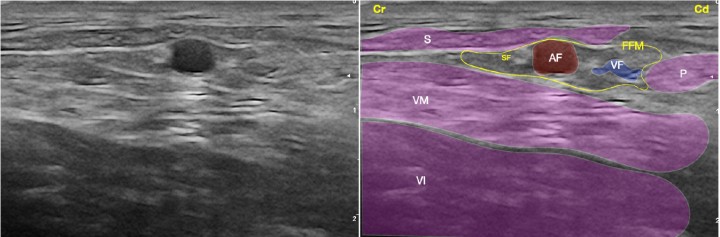

<p>Imagen ecográfica del nervio safeno (rama sensitiva distal del nervio femoral) a nivel del fémur medio. Músculo sartorio (S), músculo vasto medial (componente del cuádriceps) (VM), músculo vasto intermedio (componente del cuádriceps) (VI), músculo pectíneo (P), fascia femoral media (FFM), arteria femoral (AF), vena femoral (VF), nervio safeno (SF). Cr: Craneal, Cd: Caudal.</p>

Figura 3

Imagen ecográfica del nervio safeno (rama sensitiva distal del nervio femoral) a nivel del fémur medio. Músculo sartorio (S), músculo vasto medial (componente del cuádriceps) (VM), músculo vasto intermedio (componente del cuádriceps) (VI), músculo pectíneo (P), fascia femoral media (FFM), arteria femoral (AF), vena femoral (VF), nervio safeno (SF). Cr: Craneal, Cd: Caudal.

<p>(<strong>A</strong>) Posición del transductor y la aguja para el abordaje en plano del nervio safeno (rama sensitiva distal del nervio femoral) a nivel del fémur medio. (<strong>B</strong>) Imagen esquemática de las estructuras anatómicas y la aguja. Músculo sartorio (S), músculo vasto medial (componente del cuádriceps) (VM), músculo vasto intermedio (componente del cuádriceps) (VI), músculo pectíneo (P), fascia femoral media (FFM), arteria femoral (AF), vena femoral (VF), nervio safeno (SF). Cr: Craneal, Cd: Caudal.</p>

Figura 8

(A) Posición del transductor y la aguja para el abordaje en plano del nervio safeno (rama sensitiva distal del nervio femoral) a nivel del fémur medio. (B) Imagen esquemática de las estructuras anatómicas y la aguja. Músculo sartorio (S), músculo vasto medial (componente del cuádriceps) (VM), músculo vasto intermedio (componente del cuádriceps) (VI), músculo pectíneo (P), fascia femoral media (FFM), arteria femoral (AF), vena femoral (VF), nervio safeno (SF). Cr: Craneal, Cd: Caudal.